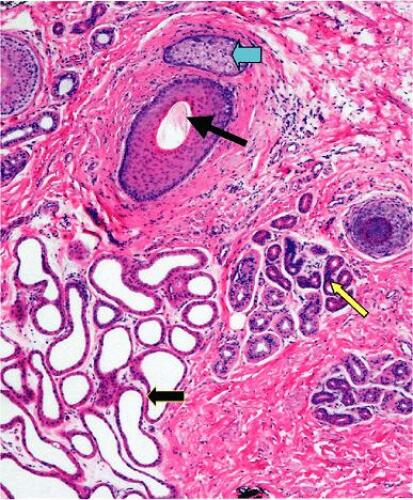

| عنوان فارسی |

کتابچه راهنمای بیماری های پوستی ساویر |

| عنوان اصلی | Sauer’s Manual of Skin Diseases |

| ویرایش | Tenth |

| ناشر | Lippincott Williams & Wilkins |

| نویسنده | Brian J. Hall, John C. Hall |

| ISBN | 9781605470771, 1605470775 |

| سال نشر | 2010 |

پوست بزرگترین عضو بدن انسان است. از بافتی تشکیل شده است که به طور مداوم رشد می کند، متمایز می شود و خود را تجدید می کند. از آنجایی که پوست یک مانع بین اندام های داخلی و محیط خارجی است، به طور منحصر به فردی در معرض عوامل خارجی مضر قرار می گیرد و همچنین بازتاب حساس بیماری های داخلی است. درک علت و تأثیر این فعل و انفعال پیچیده در پوست با درک کامل ساختار اصلی این اندام آغاز می شود.